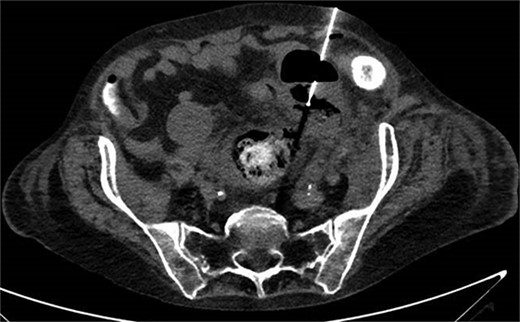

A 65-year-old female with a history of hyperlipidemia, hypertension, hip replacement, lumbar spinal fusion, chronic pain management, and prior laparotomy for endometriosis presented with a 3-day history of nausea, vomiting, and abdominal pain. She had no prior history of diverticulosis or colonoscopy. On examination, she was afebrile and hemodynamically stable. Physical examination revealed left lower quadrant tenderness, swelling, erythema, and fluctuance, suggesting an abdominal wall abscess (Figs 1 and 2). Laboratory tests showed leukocytosis with a count of 24.6 and a positive urinalysis with 2+ leukocytes. A CT scan of the abdomen and pelvis revealed a 3.8 × 3.6 cm air and fluid pocket in the low left anterior abdominal wall, indicative of an abscess likely at the site of a previous drain (Fig. 3). Additionally, there was a 2.8 × 1.8 cm irregular air pocket in the left pelvis, where an abscess had been identified in prior imaging.

CT from readmission with anterior abdominal wall abscess and left pelvic abscess.